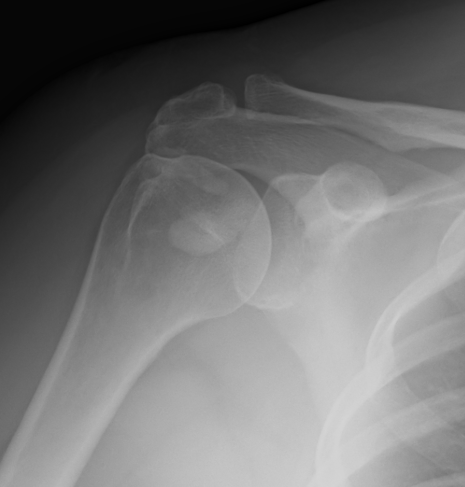

X-ray

Supraspinatous CalciumCalcific Tendonits LateralSupaspinatous Large Deposits

Supraspinatus calcification